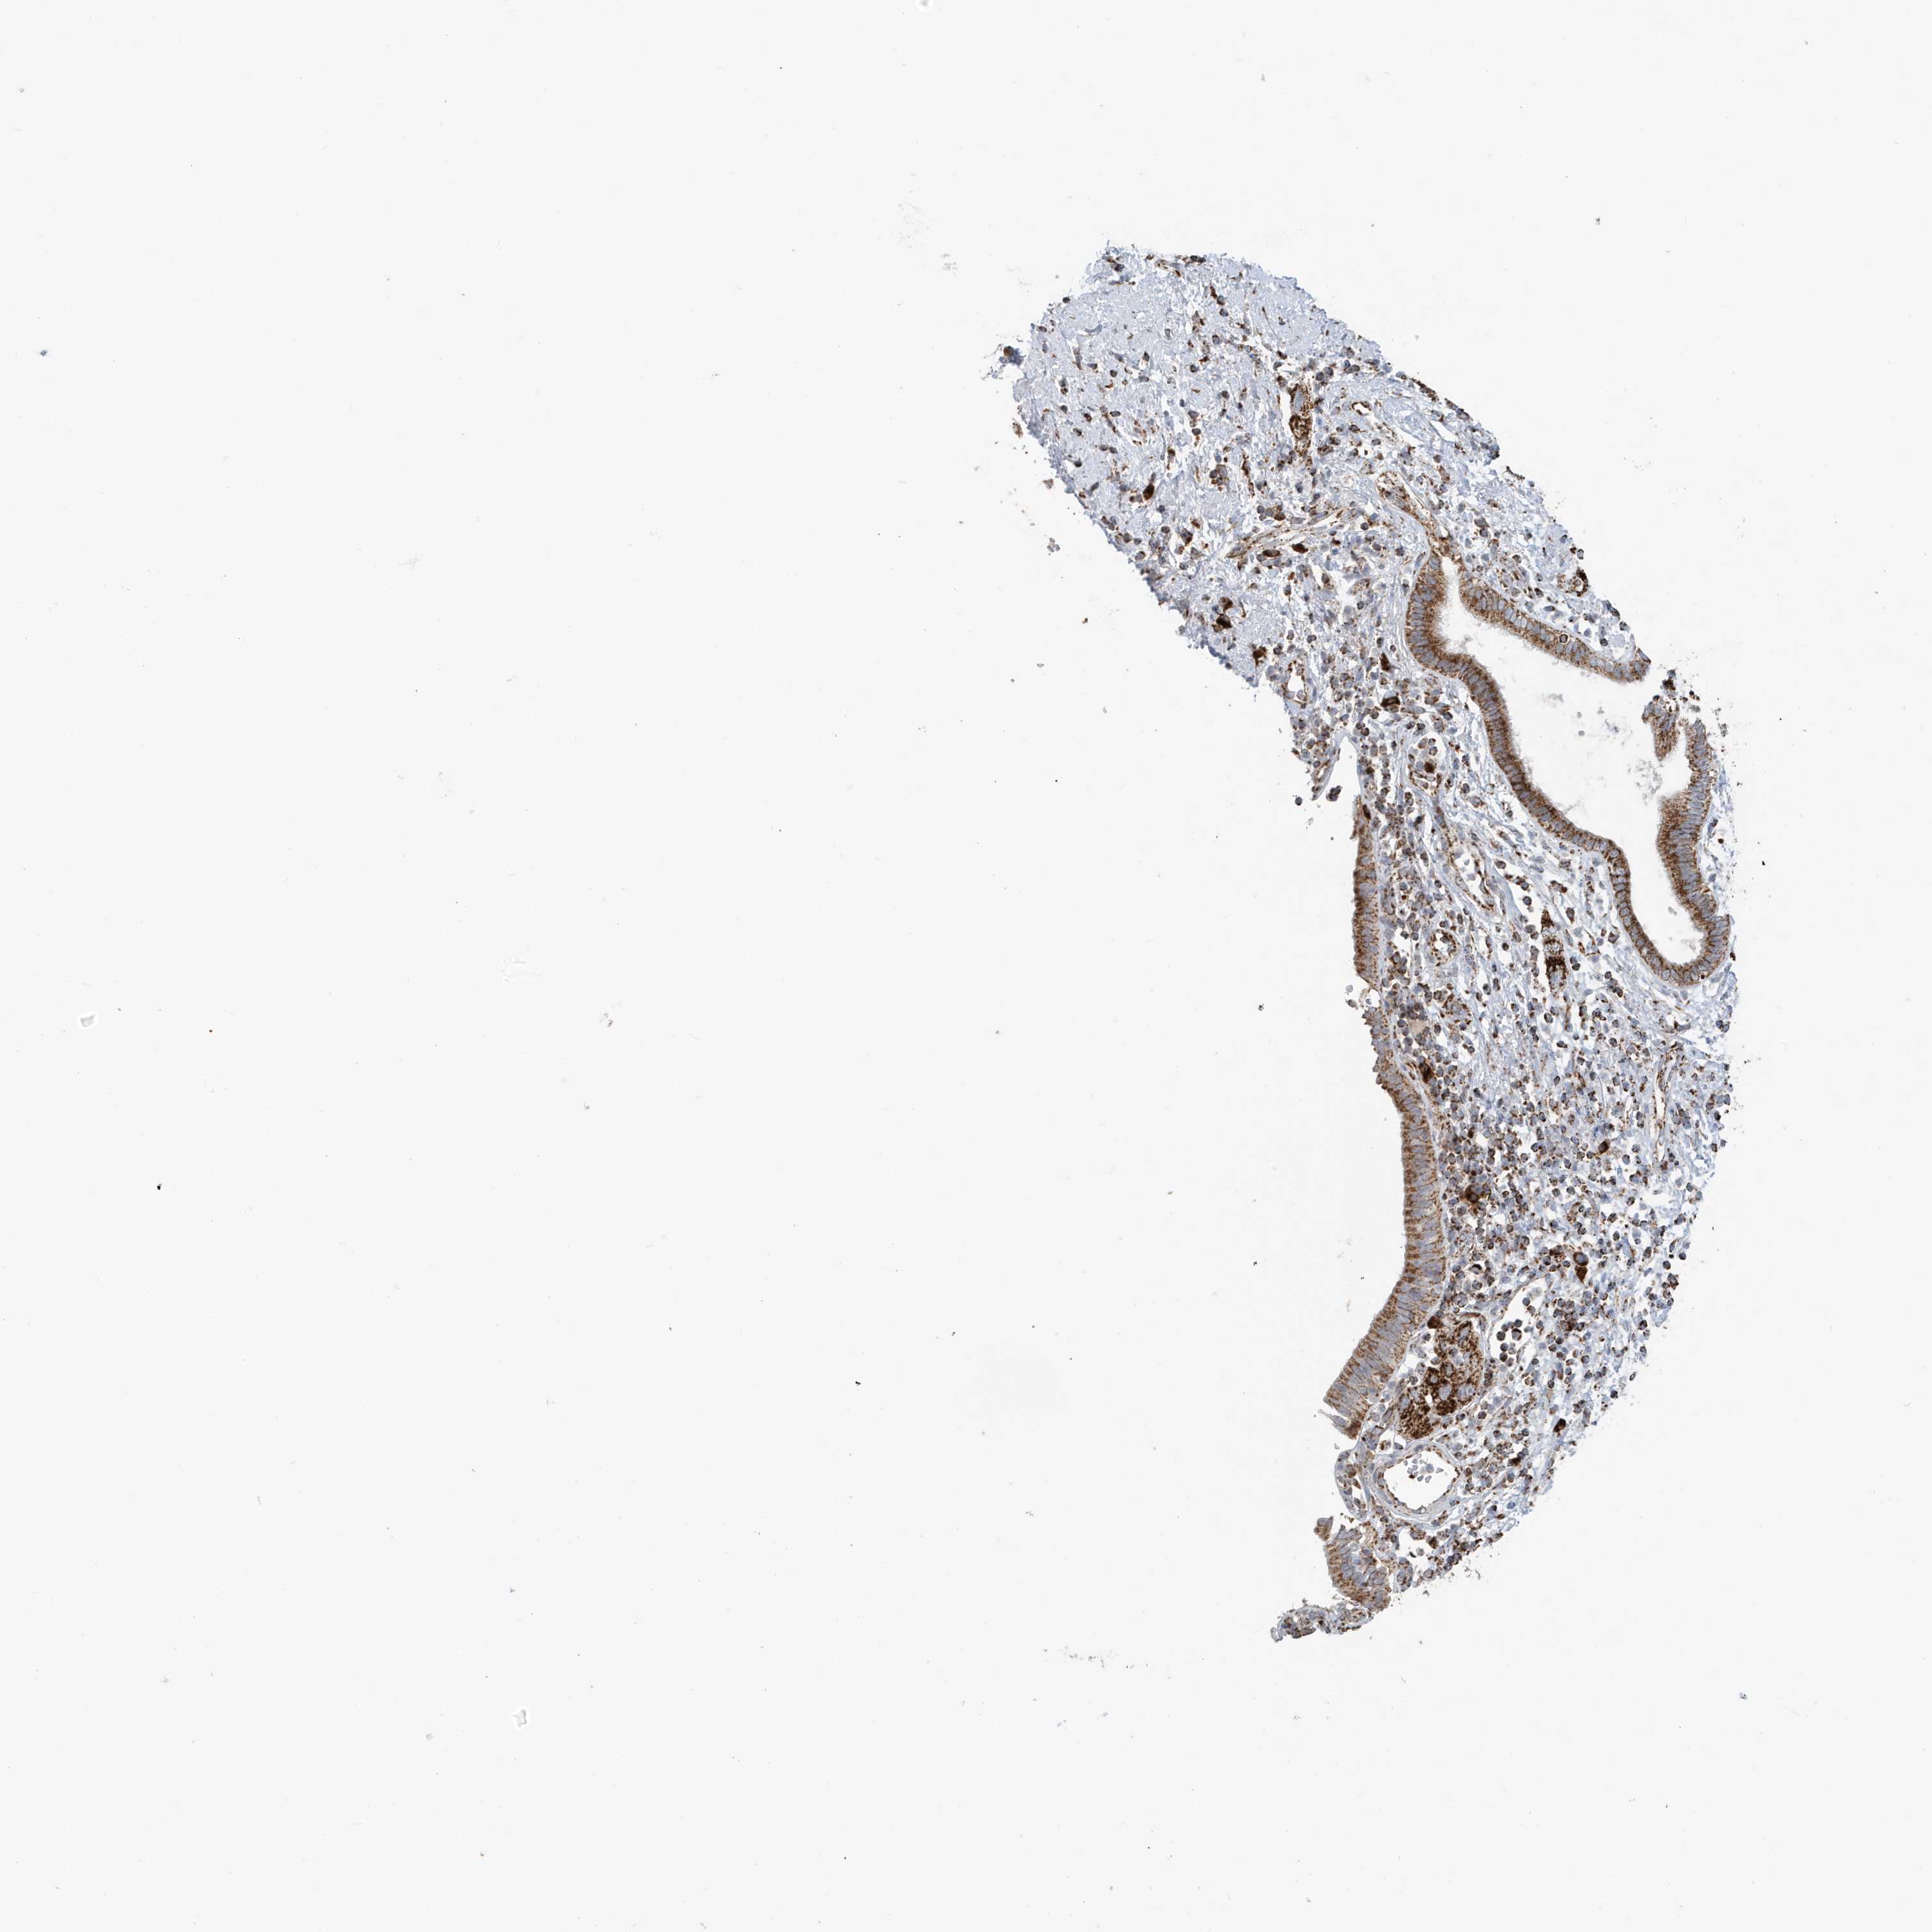

PANCREATIC CANCER - Protein expressioni

A mouse-over function shows sample information and annotation data. Click on an image to view it in a full screen mode. Samples can be filtered based on level of antibody staining by selecting one or several of the following categories: high, medium, low and not detected. The assay and annotation is described here.

Note that samples used for immunohistochemistry by the Human Protein Atlas do not correspond to samples in the TCGA dataset.

Antibody stainingi

Antibody staining in the annotated cell types in the current human tissue is reported as not detected, low, medium, or high, based on conventional immunohistochemistry profiling in selected tissues. This score is based on the combination of the staining intensity and fraction of stained cells.

Each image is clickable and will lead to virtual microscopy that enables deeper exploration of all samples and also displays staining intensity scores, fraction scores and subcellular localization as well as patient and tissue information for each sample.

Antibody HPA053198

Antibody HPA063561

Antibody CAB037058

Staining

High

Medium

Low

Not detected

Intensity

Strong

Moderate

Weak

Negative

Quantity

>75%

75%-25%

<25%

None

Location

Nuclear

Cytoplasmic/membranous

Cytoplasmic/membranous,nuclear

Adenocarcinoma, NOS